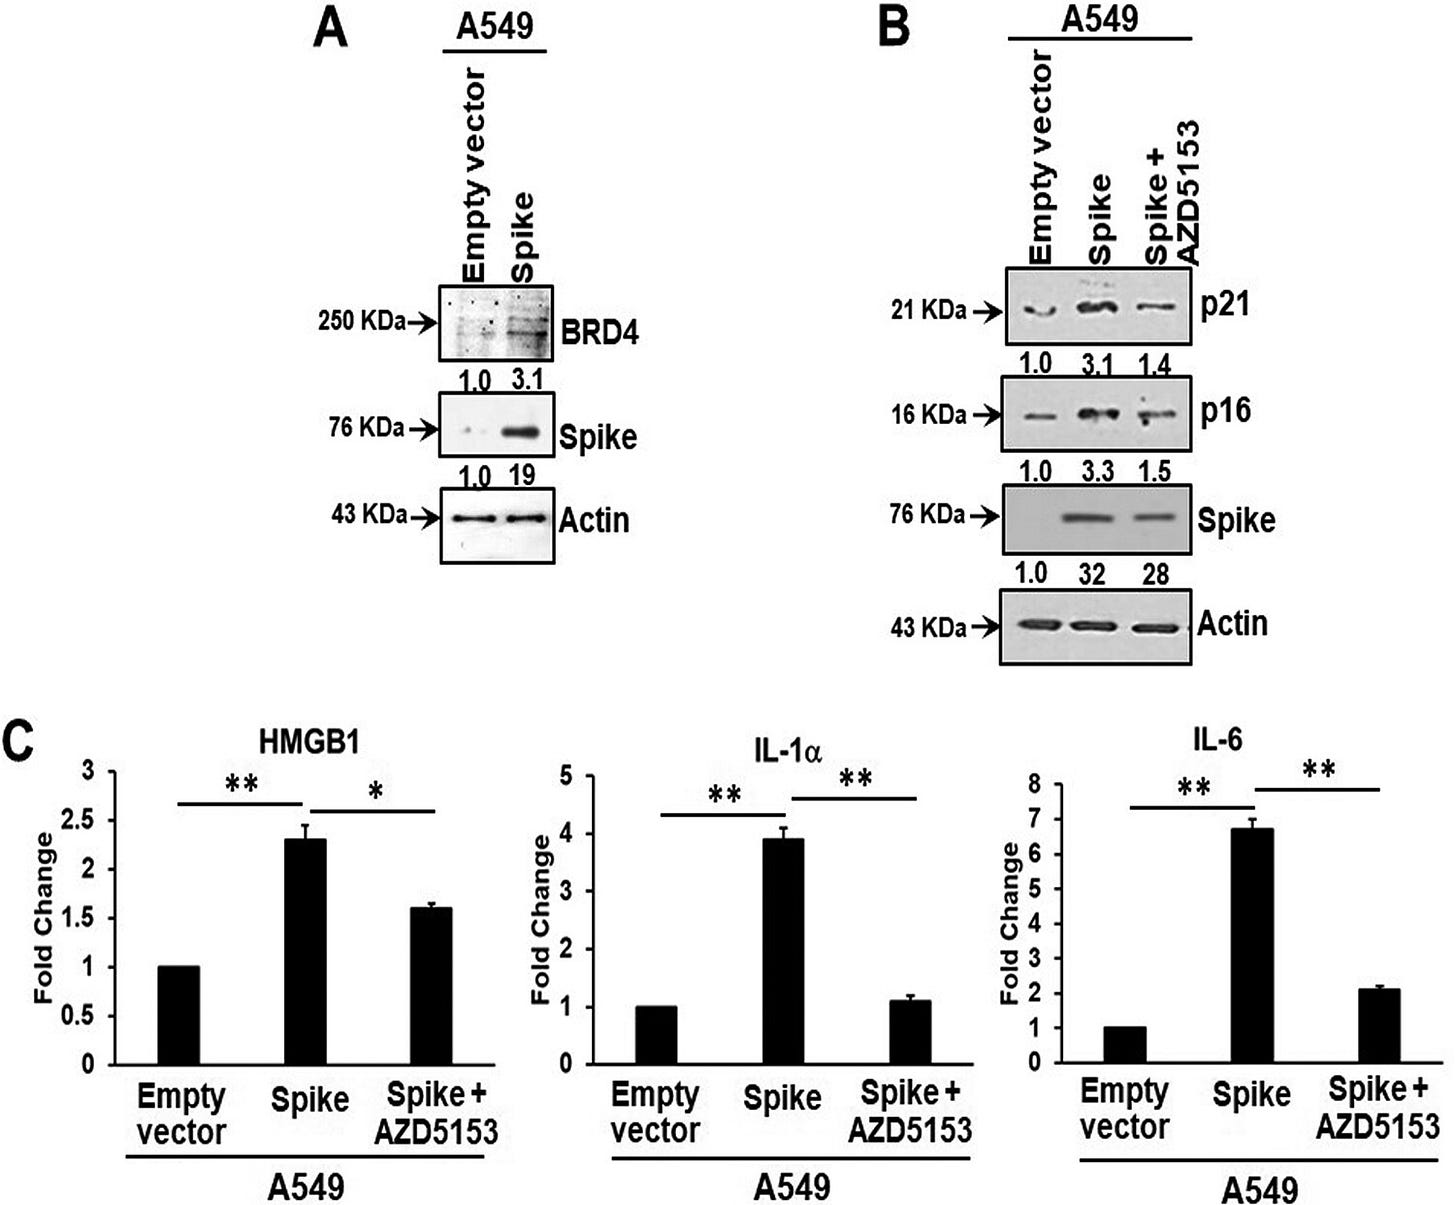

A BRD4 inhibitor reverses the senescent effects of spike on epithelial cells:

Introduction of the bromodomain-containing protein 4 (BRD4) inhibitor AZD5153 to senescent epithelial cells reversed this effect and reduced SASP-related inflammatory molecule release in TMNK-1 or EAhy926 (representative human endothelial cell lines), when cells were exposed to cell culture medium (CM) derived from A549 cells expressing SARS-CoV-2 spike protein. Cells also exhibited a senescence phenotype with enhanced p16, p21, and senescence-associated β-galactosidase (SA-β-Gal) expression and triggered SASP pathways.

For instance, BRD4 inhibitor AZD5153 represses spike induced BRD4-mediated SASP:

Bromodomain-containing protein 4 (BRD4) is a novel regulator of the senescence mechanism. BRD4 expression is required in senescence immune surveillance and SASP-associated signaling (15). Spike gene transfection of A549 cells led to an enhanced expression of BRD4 (Fig. 3A). A549 cells were transfected with the SARS-CoV-2 spike protein and incubated for 48 h prior to exposure for 16 h to the BRD4 inhibitor AZD5153. Spike protein expression induced p21 and p16 senescence markers, the levels of which were reduced by the addition of AZD5153 (Fig. 3B). Spike-transfected A549 cells exhibited enhanced secretion of SASP-related inflammatory molecules like the alarmin HMGB1 and cytokines interleukin 1α (IL-1α) and IL-6.